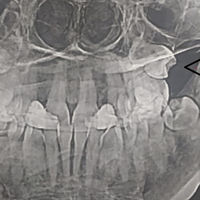

Жительница Самары обнаружила, что в гайморовых пазухах у нее выросли зубы, сообщает ГТРК «Самара».

Об этом женщина узнала, сделав МРТ. Выяснилось, что «четверки» (зубы которые идут после клыков) выросли вместо челюсти в носу.